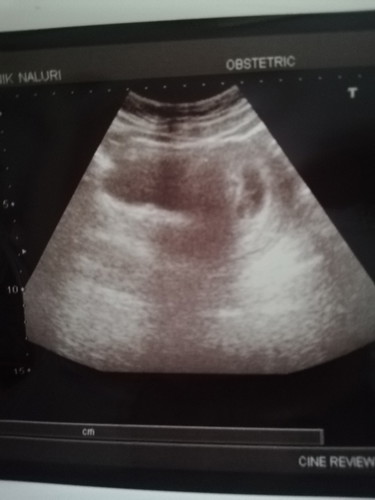

Hai semua Nak tnya.saya hamil 8 minggu 61 days.saya scan baby masih kecil jntong belum nmpak dktr suggest untk digugurkan.tetapi saya tak nak.sbb baby dh membesar 1.31cm.so dktr bagi peluang 2 mnggu dri sekarang kalau still takde perkembgan akan digugurkan.ada yg pernah mengalami mcm saya? kalau scan dktr luar dia cakap dh ada jntng but too small.mula scan masa 1 month pn kantong n baby blum nmpak.then ni 2nd scan dkt hsptl krajaan.dh nmpak baby tapi bentuk tak sama dgn usia kndungan .ada tips lain tak yg boleh selamatkan baby?